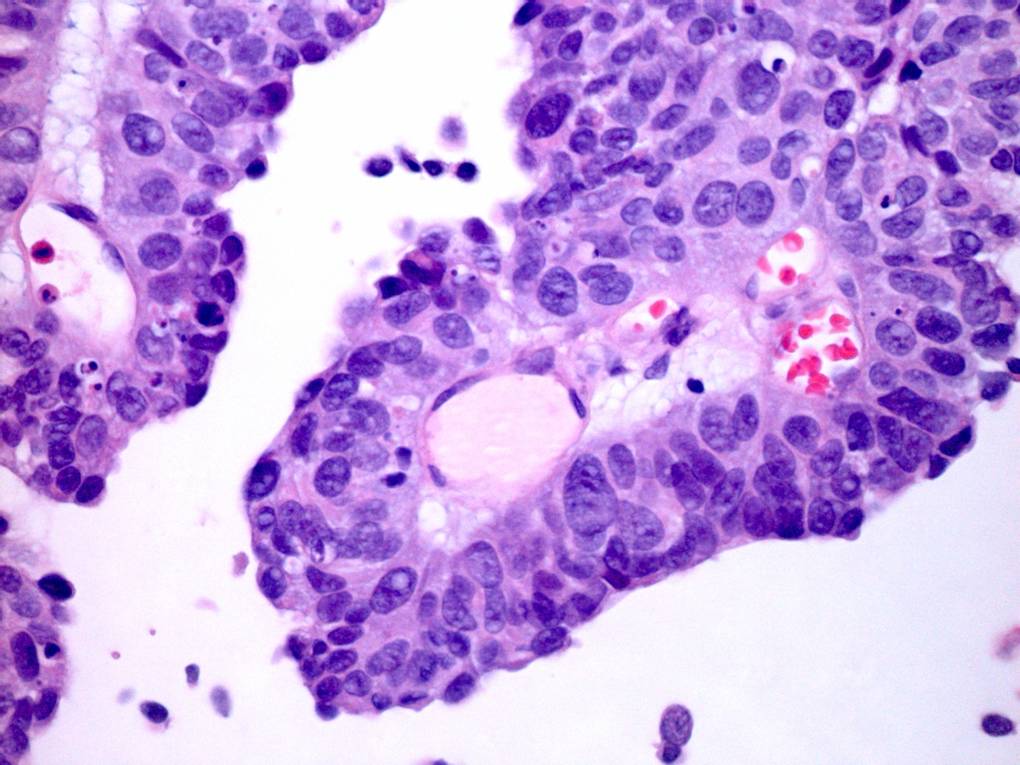

Consensus grade: High-grade papillary urothelial carcinoma (HG-PUC)

Case description (by case creator):

65 year old male. From TURBT. Diagnosis illustrated = high grade papillary urothelial carcinoma